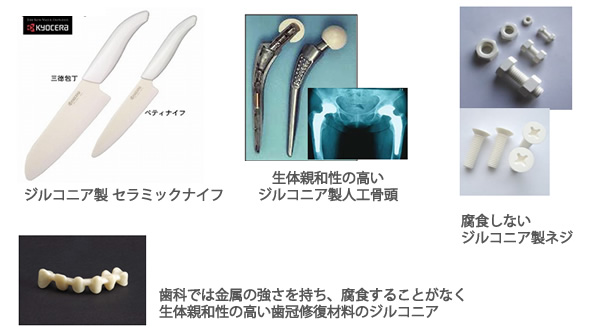

ジルコニアセラミックとは?

ジルコニアセラミック

審美歯科治療に使用する素材のひとつです。

酸化ジルコニウム(ZrO2)は、ダイアモンド類似石として人工ダイアモンドと同元素を持つ素材で、強さと美しさを持つ新しい歯冠修復セラミックです。